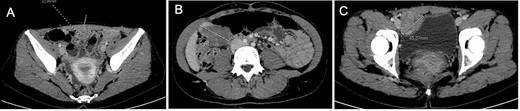

After tumor board discussion, hormonotherapy was recommended. One month after starting Letrozole, the patient expressed her desire for pregnancy and the treatment was switched to ulipristal acetate 5 mg per day. After 3 months of treatment, the abdominal pain persisted without any improvement and MRI re-evaluation showed stability compared with the previous CT (Fig. 3A–C). Given the inefficacy of this treatment, letrozole 5 mg per day was resumed in association with a Gonadotrophin-releasing hormone (GnRH) agonist (Triptorelin 12.5-mg intramuscular 1/month). After 3 months of treatment, MRI revealed a 10% reduction in the size of the three nodules (Fig. 3D–F). Abdominal pain was partially improved and localized in the right hypochondrium. The tumor board proposed MRI reevaluation after 6 months of effective treatment and surgical excision if the symptoms persisted.

Comparative magnetic resonance imaging (MRI). (A–C) MRI after 3 months of acetate ulipristal. (A) Tumor in contact with infra-umbilical linea alba; (B) lesion located in right hypochondria; (C) tumor situated in right iliac fossa near bladder. (D–F) MRI after 3 months of AI and GnRH agonist. (G–I) preoperative MRI.

Treatment was pursued for another 3-month cycle with persistent abdominal discomfort. Control MRI showed the persistent benefit and stability of the three lesions (Fig. 3G–I). Laparoscopy was performed after a total of 6 months of AI and GnRH agonist. Inspection of the abdominopelvic cavity revealed three tumors located in the right hypochondrium, the left para-vesical fossa and the median trocar scar infiltrating the abdominal wall. All three lesions were excised (Fig. 4). Definitive histopathological results showed spindle-cell proliferation of smooth muscle cells (Fig. 5). There was no nuclear atypia, necrosis or mitosis, but the proliferation seemed modified with edema and fibrosis, probably due to the treatment. Tumor cells were smooth muscle actin-, desmin- and caldesmone-positive, confirming their smooth muscle nature. They were CD117- and HMB45-. Ki67 was close to 1%.